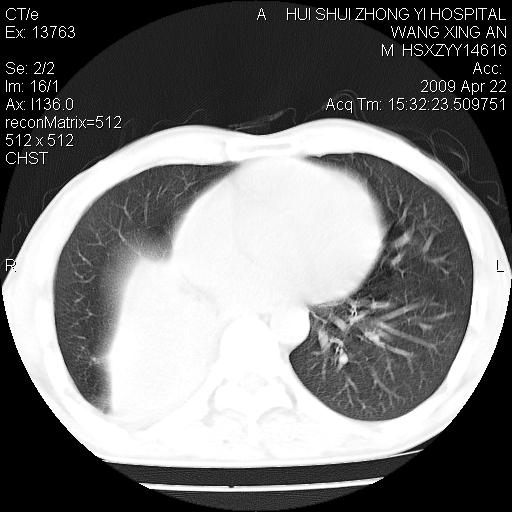

标题: CT19534:患者男、46岁咳嗽、胸痛半月。 [打印本页]

标题: CT19534:患者男、46岁咳嗽、胸痛半月。

考虑---右肺中心型肺癌继发下叶不张,少量胸水。

支持右侧中央型肺ca并右下肺不张、右侧胸腔少量积液。

1、右下肺中央型肺癌并右肺转移,右肺下叶不张。(右肺有结节影)。

2、右中上肺陈旧性肺结核(因为大多为纤维灶)。

3、右侧胸腔积液。

1、右下肺中央型肺癌并右肺转移,右肺下叶不张。(肿块围绕右肺下叶支气管生长,致管腔闭塞右肺下叶不张;右肺有结节影)。

2、右侧胸腔积液。

3、右中上肺陈旧性肺结核(右肺见纤维化病灶及点状钙化)。